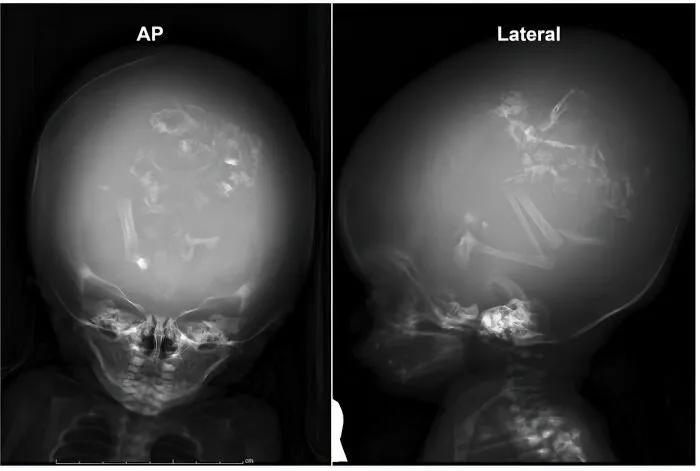

19. 3 близнеца-паразита в черепе двухмесячного ребенка